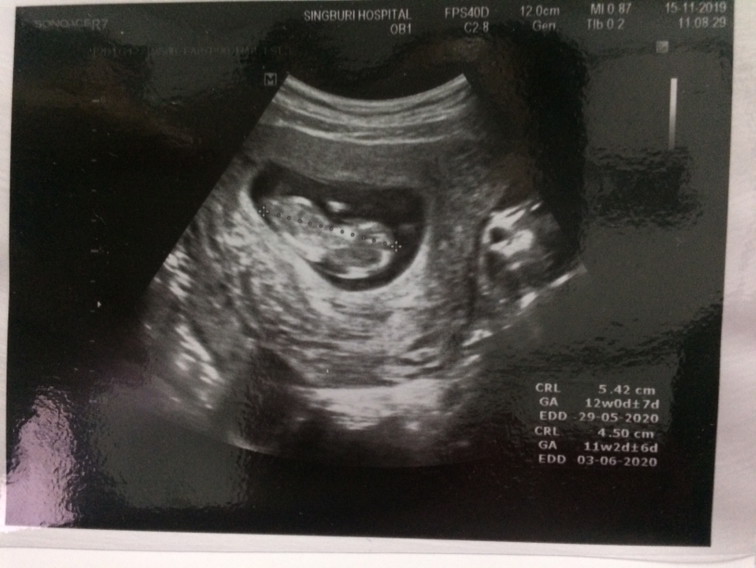

12 สัปดาห์ค่ะ

ตอน 12 week ค่ะ